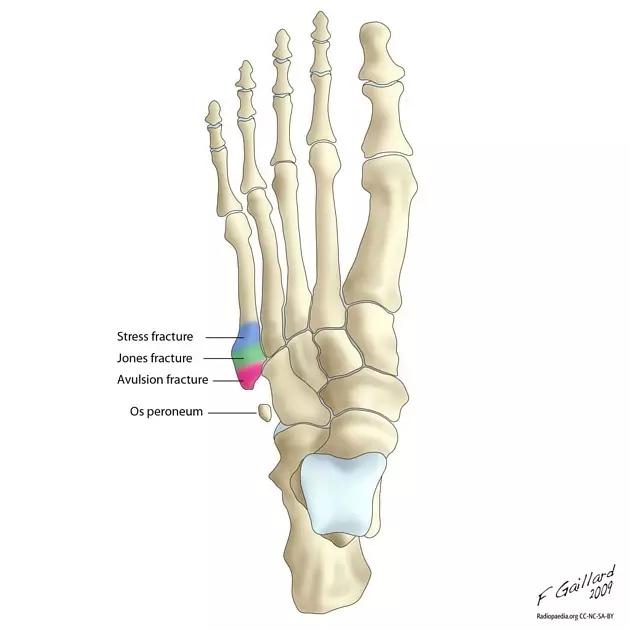

14.第五跖骨骨折

第五跖骨基底部骨折的不同类型:Stress 骨折;Jones 骨折:第五跖骨基底部以远 1 英寸内的骨折称为 Jones 骨折; Avulsion 骨折。

(来源:Radiopaedia)

Stress 骨折(来源:OrthoInfo-AAOS)

Jones 骨折正位片(来源:Radiopaedia)

Jones 骨折斜位片(来源:Radiopaedia)

第五跖骨骨折还有 dancer’s fracture。

dancer’s fracture 正位片(来源:footEducation)

dancer’s fracture 侧位片(来源:footEducation)